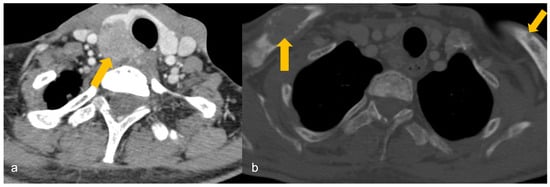

The patient is scanned with mild neck extension using a linear array high-frequency probe (7.5–15 MHz) in transverse and longitudinal planes with a special focus behind the thyroid gland medial to the carotid and jugular vessels where the parathyroid glands are usually located [18]. The neck should be scanned from the carotid bifurcation to sternal notch and the paratracheal spaces, carotid-jugular axis, and thyroid gland should be included [79]. PA is a well-circumscribed, oval- or oblong-shaped, hypoechoic lesion compared to the adjacent thyroid gland, located posterior (more commonly), anterior or lateral to the thyroid at the superior/inferior polar regions, having an echogenic capsule, and shows an enlarged feeding inferior thyroidal artery (feeding vessel sign) on colour Doppler with a low resistive index on spectral Doppler [1,18]. Internal heterogeneity due to fat, calcifications or haemorrhage can be seen [1]. US of a PA is shown in Figure 1.

Figure 1.

(a,b): Parathyroid adenoma on ultrasonography in a patient with primary hyperparathyroidism. (a) A well-defined oval-shaped homogeneously hypoechoic lesion (arrowhead) lateral to the left lobe of thyroid gland (shown by 1, 2 and + sign). (b) Colour Doppler image shows feeding vessel sign (arrowhead). Imaging findings are suggestive of parathyroid adenoma.